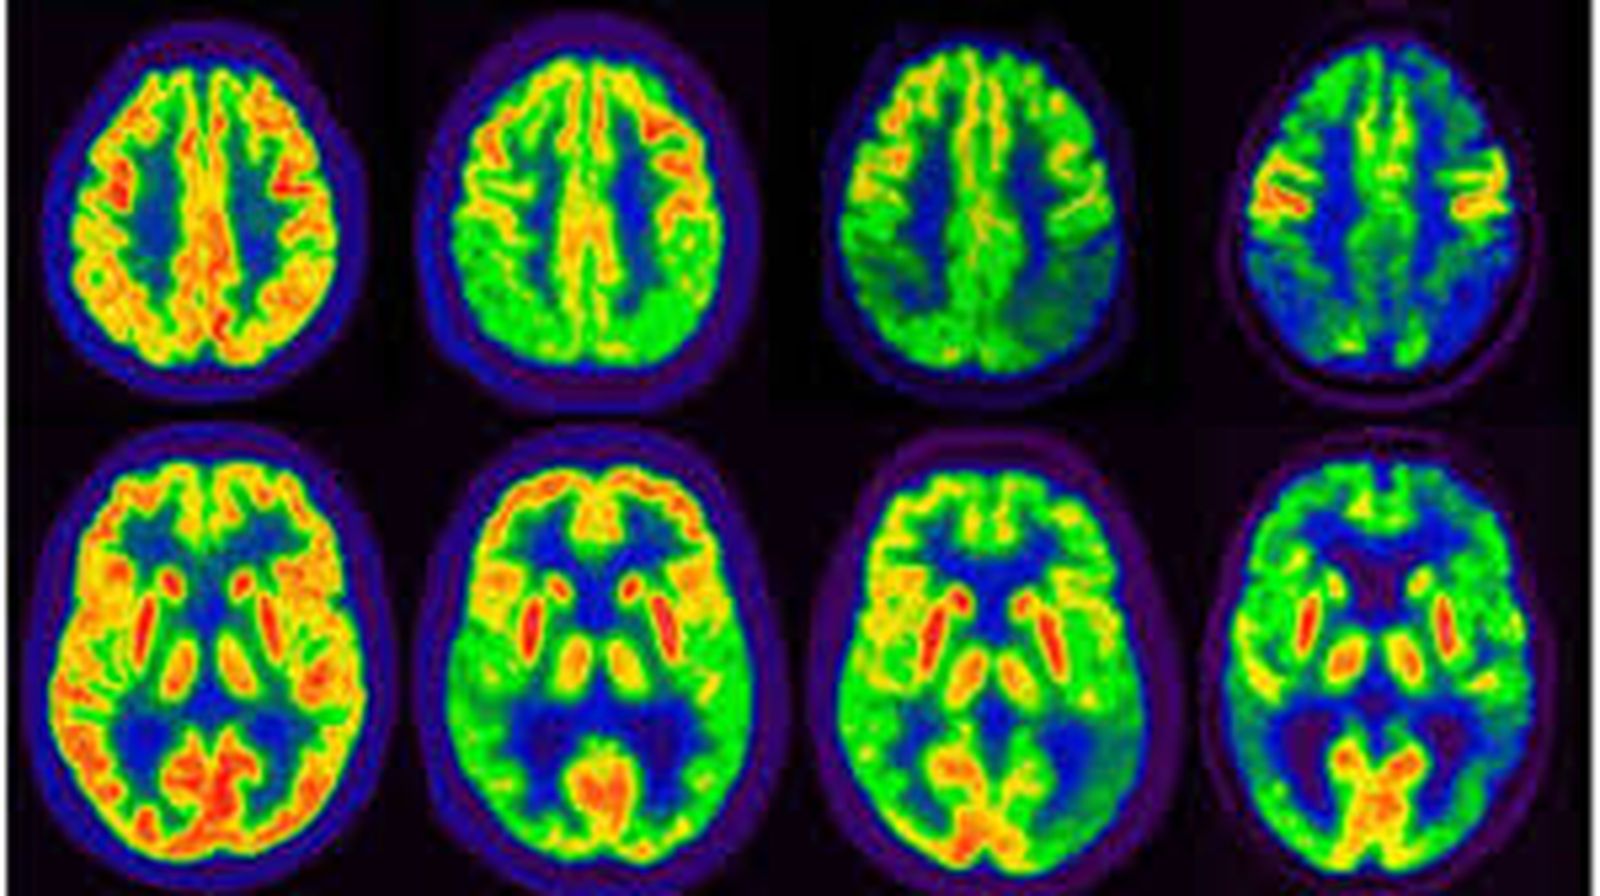

Aunque sea a salto de mata, no quisiera dejar pasar este día sin atraer un momento la atención de los seguidores de este blog sobre “otra peste”, de la que hoy se habla mucho menos que de la Covid-19 y cuya persistencia en el tiempo y en los medios ha reducido prácticamente a una rutina molesta más de nuestras vidas hasta el punto de que, de no estar directamente afectados por ella, preferimos orillar o pasar de puntillas por su escenario. Me estoy refiriendo a que hoy se celebra el “día mundial del alzhéimer”, la enfermedad neuronal degenerativa que lentamente va reduciendo a polvo la condición humana, en lo espiritual y en lo físico, no solo de los pacientes, sino también de muchos de sus cuidadores.

En estos momentos, en España cabe hablar de más de ochocientos mil enfermos de alzhéimer y de, por lo menos, dos millones más de personas afectadas como cuidadores principales o de apoyo. Así, ¡casi tres millones de españoles se las ven todos los días con esta danza macabra de la condición humana, muy agravada por la longevidad que hoy ya alcanzamos, desorientados frente a un fenómeno que mata mucho antes de que el enfermo muera y que sume en la más absoluta impotencia a cuantos se mueven a su alrededor! Aunque a nada conduzcan las comparaciones por lo de que a cada palo le toca aguantar su vela, lo cierto es que, para darnos cuenta a fondo de este drama, basta pensar que se trata de una peste muy similar a la mencionada del coronavirus, la pandemia que nos acongojó de tal manera que pudimos aguantar, no solo sin rechistar, sino también aplaudiendo, largos meses confinados en angosturas a veces más atosigantes que los muros de una cárcel. Digamos, para abundar en los rasgos más dramáticos de la tragedia, que mientras el grueso de esta peste parece que podrá dilucidarse o diluirse, como estamos viendo, en un par de años, la del alzhéimer corroe el cuerpo del enfermo y el espíritu de su cuidador a veces durante un porrón de años.